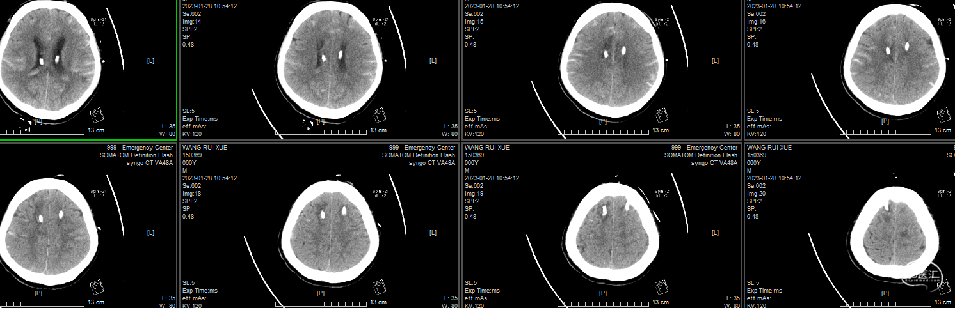

头颅CT(术后第一天):

前交通动脉瘤支架术后改变;双侧脑室引流术后改变;胼胝体脑出血、脑室积血有减少;蛛网膜下腔积血稍有增多。

侧脑室有松动,但四脑室积血增多,脑干和小脑受压加重,和预判的一样。

第二次术后第一天头颅CT(01-23):

脑室积血明显减少,四脑室减少一半,形成液平面,三脑室也开通了。继续引流。

位置满意。

二次术后第六天头颅CT(01-28)复查:

前交通动脉瘤支架术后、双侧脑室引流术后无著变,右枕部穿刺术后改变,残留脑出血、脑室积血、蛛网膜下腔积血略有吸收。

四脑室基本干净。

入院

第一天

第二天

第七天

第十三天